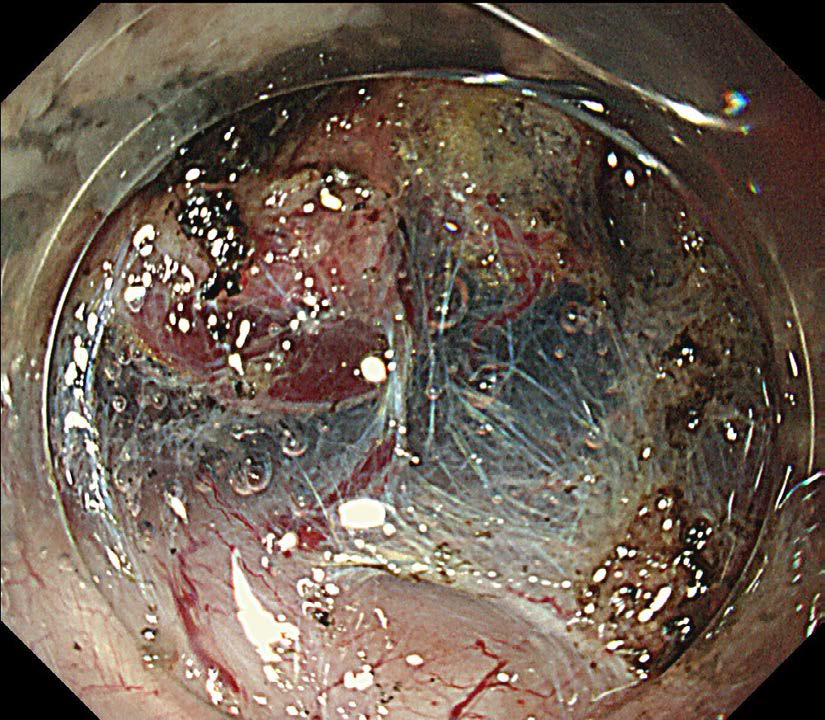

迅速な止血処置をサポート

GIF-H290Tでは副送水口の位置を改善。処置具の近くに送水することで、迅速な止血処置をサポートします。